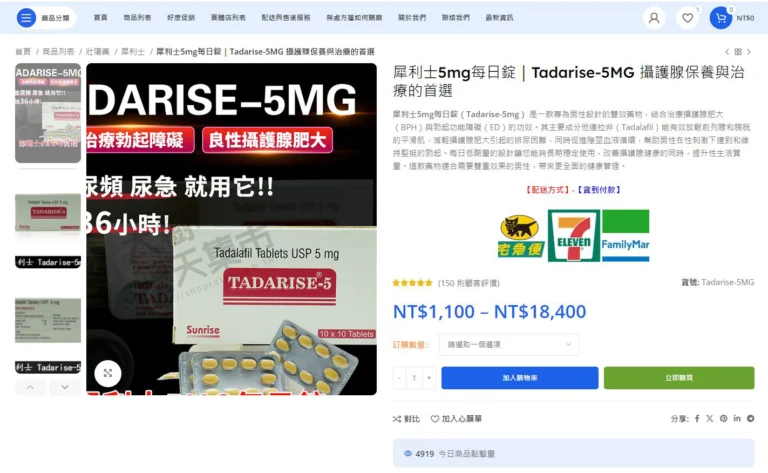

網路藥局是當前最方便的購買渠道之一,您可以直接在線上下單,享受送貨到家的服務。大多數大型網路藥局提供正品藥物、價格透明,並提供專業的藥師咨詢服務。

- 大樹藥局(https://greaoptree.com.tw/):大樹藥局提供多款犀利士產品,保證正品,且支持宅配與超商取貨服務。

- 大樹露天購物網(https://rutenshop.com.tw/):提供犀利士5mg每日錠,並有專業藥師的在線咨詢服務,方便且可靠。